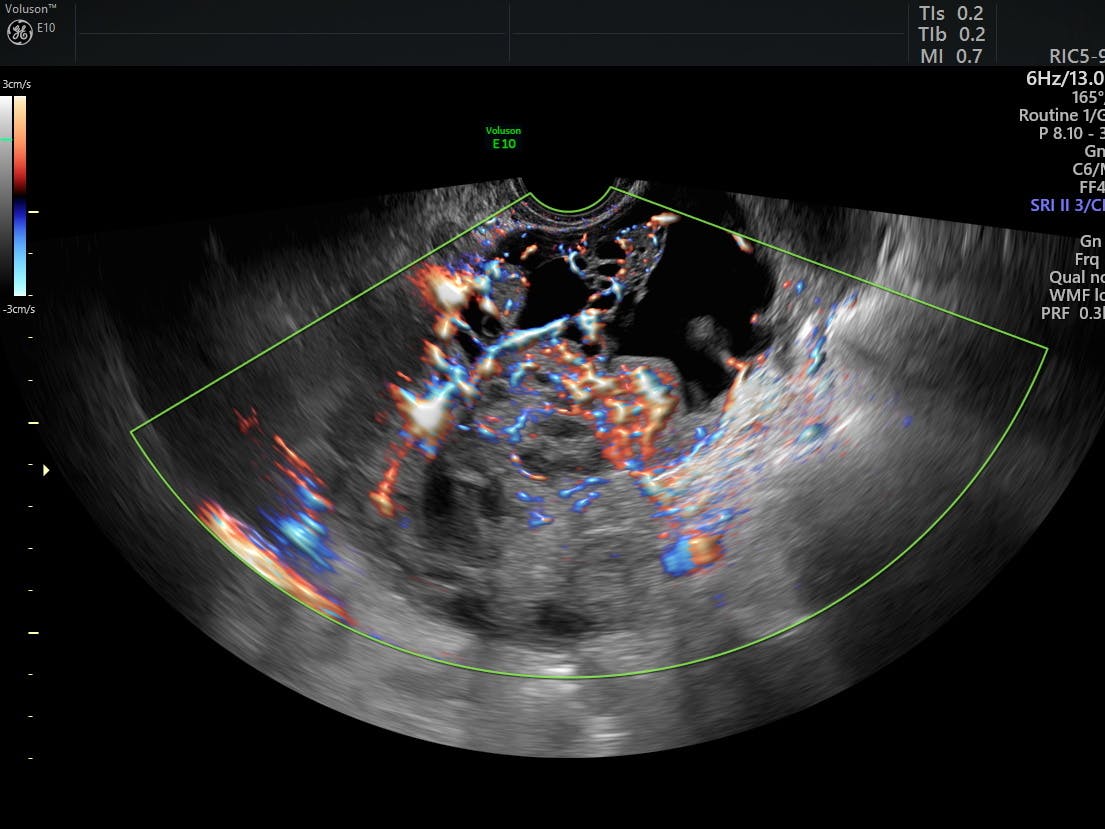

Transvaginal Color Doppler Ultrasound Showing A Cervical Cancer With Download Scientific Diagram

Transvaginal Color Doppler From A Cervical Cancer Showing An Abundant Download Scientific Diagram

Neoangiogenesis In Early Cervical Cancer Correlation Between Color Doppler Findings And Risk Factors A Prospective Observational Study World Journal Of Surgical Oncology Full Text